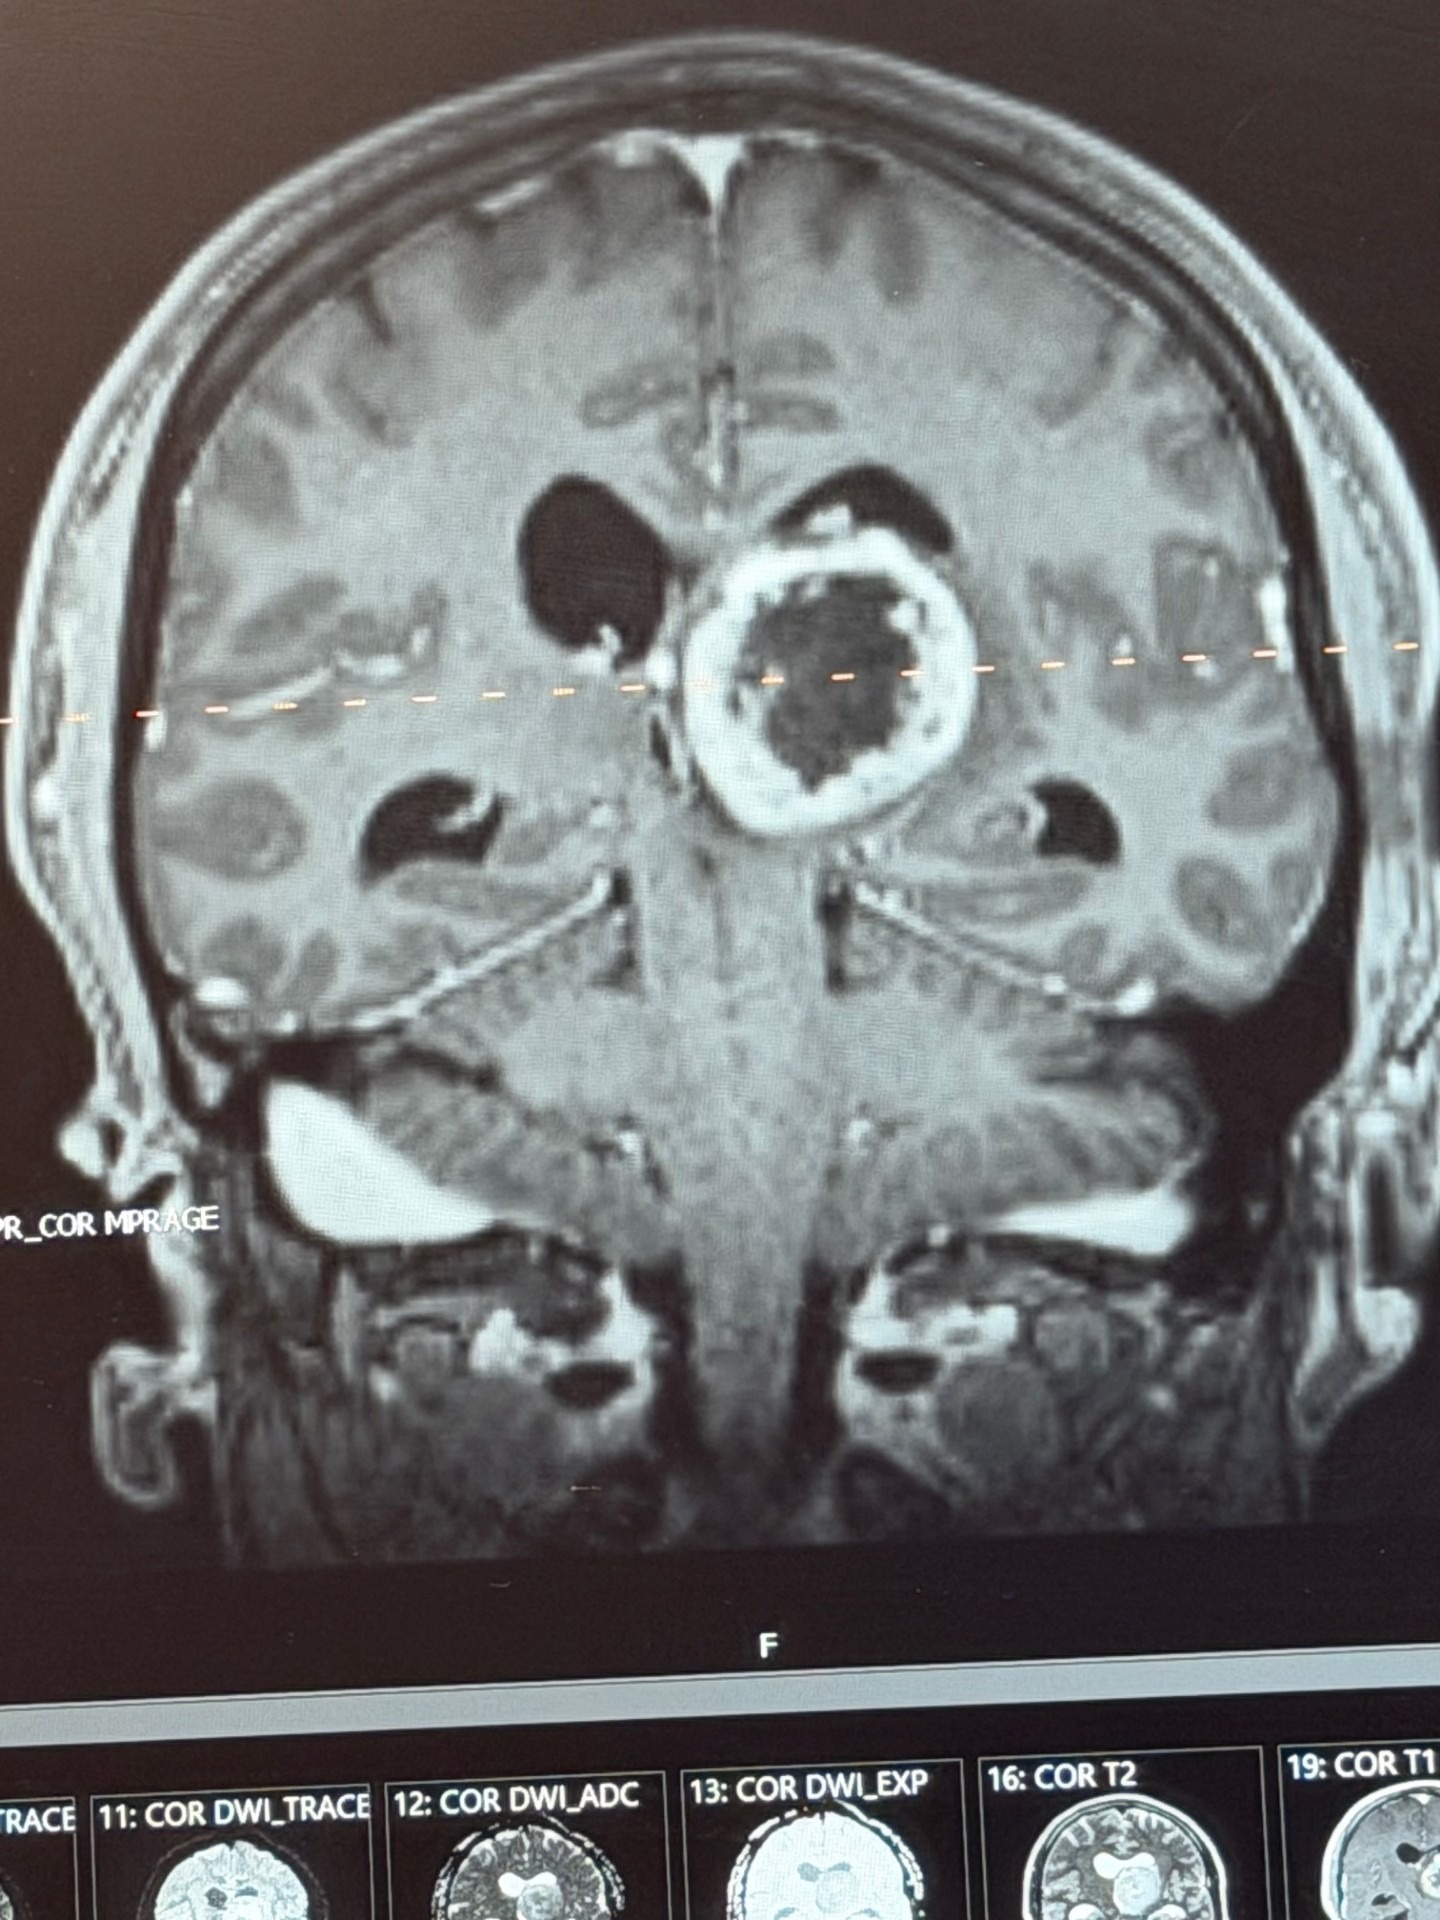

My name is Matthew, and I’m reaching out because I’m facing one of the toughest challenges of my life. I was recently diagnosed with a high-grade glioma in my brain stem. It all started when I went to the hospital with a headache, and after some head scans, the doctors found a mass. A brain biopsy revealed it was very aggressive and required fast, aggressive treatment. Everything changed so quickly, and I’m now preparing for a four-week treatment plan that will be both physically and emotionally demanding.